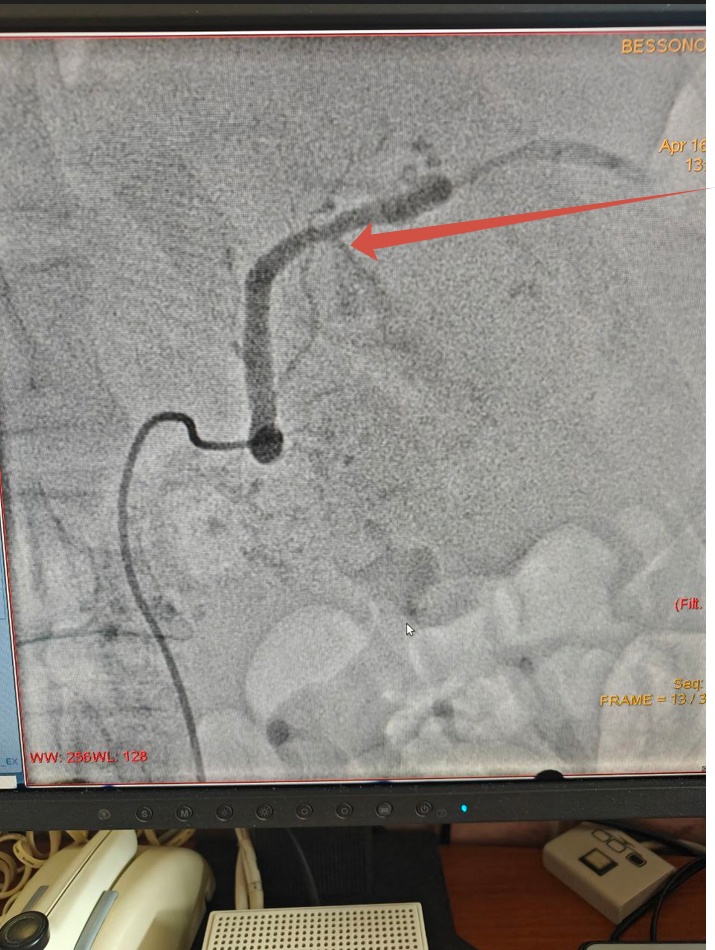

Фото: ГУЗ "Липецкая областная клиническая больница"

Рентгенэндоваскулярные хирурги Липецкой областной клинической больницы спасли жизнь 52-летнего пациента с внутренним кровотечением. Все случилось в конце прошлой недели, когда мужчина обратился с жалобой из-за обострения хронического заболевания. Во время обследования врачи Владимир Анисимов и Алексей Литвиненко заподозрили, что в селезеночной артерии находится аневризма.

— Во время операции была обнаружена причина повреждения артерии — хронический воспалительный процесс поджелудочной железы, который «разъел» сосудистую стенку. В результате дефект сосуда привел к внутреннему кровотечению, — пояснили медики.

За 6 часов операции хирурги не только эмболизировали артерию, но и остановили открытое кровотечение. Сейчас пациент находится в реанимации. Липчанину предстоит длительное лечение основного заболевания.